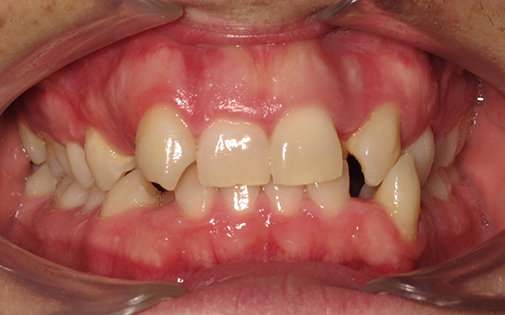

This patient presented with a very severe malocclusion (i.e. irregularity of her teeth and jaws). The ideal treatment recommended was removal of four teeth, upper and lower fixed braces and surgery to her jaws. However, the patient was not keen on the idea of surgery so she offered the alternative of removal of two upper teeth and Invisalign clear aligners. With the expertise of our specialist orthodontists, even the most challenging cases can be treated successfully with Invisalign.